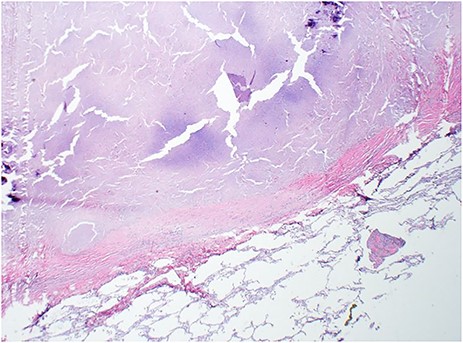

A 58-year-old man with idiopathic pulmonary fibrosis listed for lung transplantation received a donor lung offer from a 46 year old non-smoking brain dead female donor. Prior to us receiving the offer, the donor lungs had been rejected by three other centers. The Lung Allocation Score for their three recipients ranged from 51.4 to 89.87. The donor blood gasses revealed excellent oxygenation with a PaO2 of 567 mmHg. Chest radiograph, however, revealed a large calcified mass confirmed on computed tomography (CT) as a 3 cm × 3 cm mass in the left lower lobe of the lung (Fig. 1). CT imaging of the abdomen and pelvis revealed a cystic right ovarian lesion measuring 7.3 cm × 4.2 cm × 4.8 cm. The presence of large pulmonary and ovarian masses created initial doubt and hesitation about the safety of using the lungs for transplantation. Due diligence was exercised and discussions were conducted with multiple team members and radiologists. Radiologic appearance of both (pulmonary and ovarian) masses was deemed to be benign and the lungs were accepted. Ovarian biopsy at procurement confirmed a benign mucinous cystadenoma. Bilateral sequential lung transplantation was performed along with backtable wedge resection of left lower lobe lung mass prior to implantation of the left lung. Grossly, the cut surface of the mass had a chalky white appearance. (Fig. 2) Histopathologic examination revealed the pulmonary mass to be a benign hyalinized necrotizing granuloma. (Fig. 3) Postoperatively, the patient did well with no evidence of primary graft dysfunction. More than 1 year after the transplant, the recipient continues to do well with excellent functional status without any evidence of chronic lung allograft dysfunction.

H&E of left lung nodule from wedge resection with hyalinized necrotizing granuloma and surrounding normal lung parenchyma (2×).